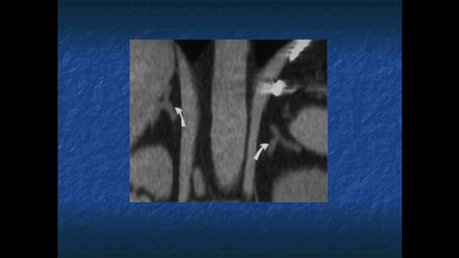

TOMOGRAFIA COMPUTARIZADA.

PERMITE IDENTIFICAR LAS GLANDULAS SUPRARRENALES EN MAS EL 95% DE LOS INDIVIDUOS, SI LOS CORTES SON DE POCO GROSOR

RESONANCIA MAGNETICA

PERMITE IDENTIFICAR LAS GLANDULAS SUPRARRENALES EN EN EL 100% DE LOS INDIVIDUOS.